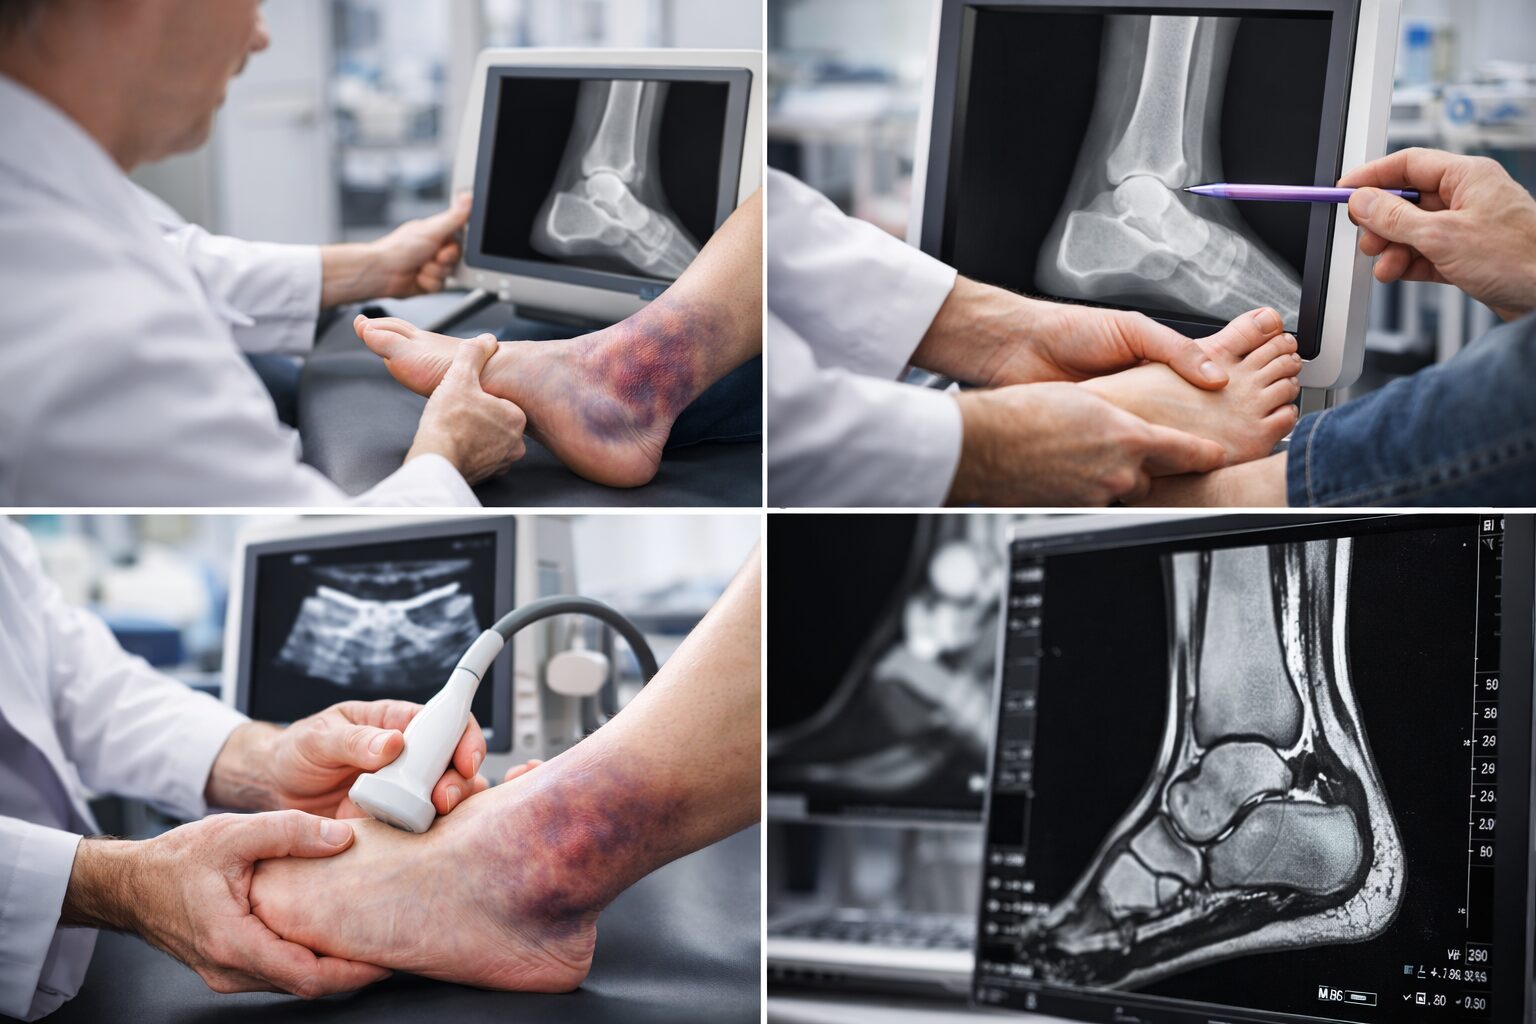

そんな疑問を持つ人もいますよね。整形外科では、医師が直接足の状態を確認する触診に加え、レントゲンやエコーなどの検査を行うことができると言われています。

これにより、見た目ではわかりづらい骨折や靭帯損傷の程度を把握しやすくなります。自己判断だけに頼らず、体の中で何が起きているのかを確認する意味でも、病院での来院は大切だと考えられています。

そう感じる人もいますが、触診に加えて画像検査を組み合わせることで、より詳しい状態確認ができると言われています。

レントゲン検査では、骨折の有無を確認する目的で行われることが多いそうです。一方、エコーやMRIでは、靭帯や軟部組織の損傷状態を把握しやすいと言われています。

これらの結果を踏まえて、安静を中心に様子を見るのか、さらに検査を進めるのかなど、今後の方針を考えていく流れになるとされています。自己判断では見えない部分を確認できる点が、病院来院の大きなメリットだと言われています。